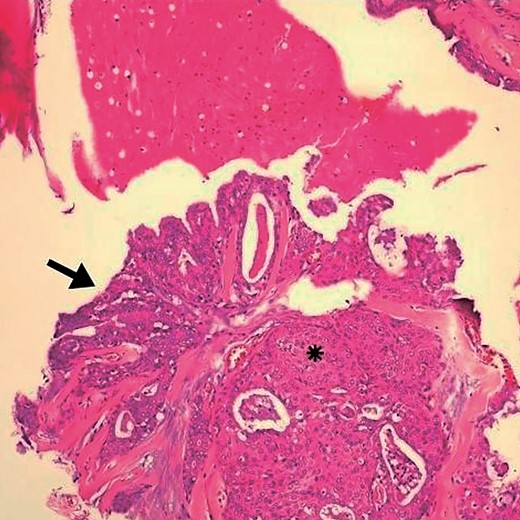

A 45-year-old female patient, who denied smoking and alcohol consumption, experienced sudden discomfort in the right parotid region with an increase in volume for a week. The discomfort lasted two days and stopped after the prescription of non-hormonal anti-inflammatories. Although the discomfort passed, the volume continued to increase. The patient denied xerostomia, a history of rheumatoid arthritis, fever, and weight loss. On palpation, a firm, deep nodular lesion measuring 5 × 4 cm was detected, forming part of the right parotid gland. Ultrasonography confirmed the diagnosis of a right parotid cyst measuring 29 × 19 × 21 mm. Fine needle aspiration cytology (FNAC) was performed, with a diagnosis of chronic parotid cyst. As the lesion persisted and increased in volume, surgery was recommended; however, the patient chose to continue with observation. In subsequent examinations, the size of the lesion increased, measuring 6 × 4 cm. She underwent right partial parotidectomy with preservation of the facial nerve, with good evolution. In the context of the cystic lesion, a well-differentiated intracystic, well-defined mucoepidermoid microcarcinoma was diagnosed, with discrete cytological atypia (Figs 1 and 2). The patient remains under periodic follow-up, with no evidence of disease after six months.

Arrows indicate the wall of a multilocular cyst without atypias. Black asterisk – non-invasive solid area with epidermoid alterations and low-grade atypias. White asterisk – invasive area with squamous and mucinous elements, suggesting the possibility of mucoepidermoid carcinoma. HE, ×4.